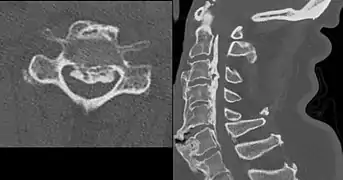

Ossification of the posterior longitudinal ligament in DISH